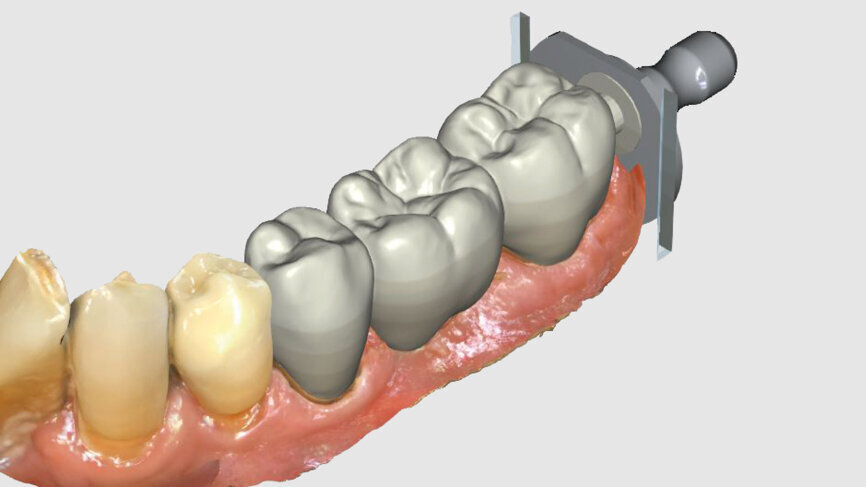

One week later, the extraction socket, which was still healing, was modelled for the ovoid pontic using an electrotome loop. The second premolar and molar were prepared as abutment teeth for a bridge. The bridge was then designed (Figs. 4–6) and milled from KATANA Zirconia Block for Bridge in Shade A3.5 and individualised with CERABIEN ZR FC Paste Stain (both Kuraray Noritake Dental; Figs. 7–10). A further week later, the bridge was luted with the self-adhesive resin cement PANAVIA SA Cement Universal after sandblasting (Figs. 11–13).

Fig. 4: Bridge design using CEREC Software.

Fig. 5: Bridge design using CEREC Software.